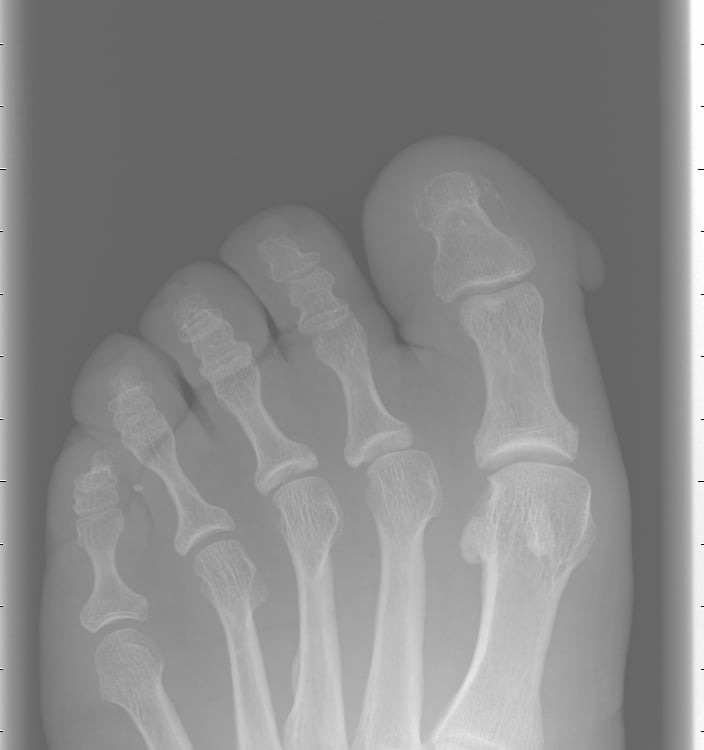

Localización: En los dedos, cerca de las uñas (periungueal) o en las falanges distales.

Examen clínico: Evaluación de la forma, tamaño y características de la lesión.